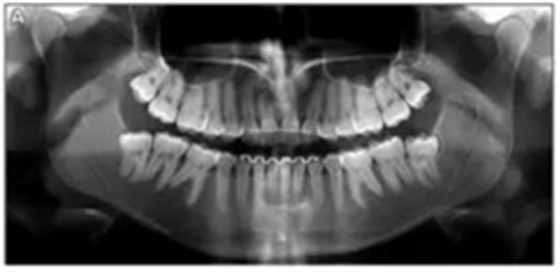

全景X線(圖3)顯示所有牙齒均存在,包括第三磨牙的牙胚。左下頜第二磨牙近中阻生。X線片顯示以前根管治療的上頜右側(cè)切牙(據(jù)報(bào)道有窩溝內(nèi)陷),對側(cè)切牙有根尖周圍病變以及窩溝內(nèi)陷的典型影像學(xué)表現(xiàn)。上頜中切牙的根部顯示先前存在的吸收。頭影測量分析顯示上頜骨和下頜骨矢狀和垂直關(guān)系正常。上頜和下頜門牙過度唇側(cè)傾斜。

6年后治療結(jié)果保持穩(wěn)定(圖11,圖12 ; 圖13)??梢杂^察到穩(wěn)定的間隙關(guān)閉,正常的覆蓋和覆合,上下牙中線一致,微笑美觀。建議完美替代了拔除的側(cè)切牙。正畸治療后進(jìn)行牙齒美白。